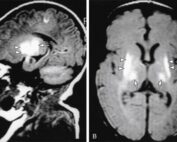

Tumores cerebrales: Un panorama general

Los tumores cerebrales representan un desafío médico complejo y preocupante en la actualidad. Estas neoplasias, que se forman en el tejido cerebral, pueden tener consecuencias graves para la salud y el bienestar de los pacientes. [...]